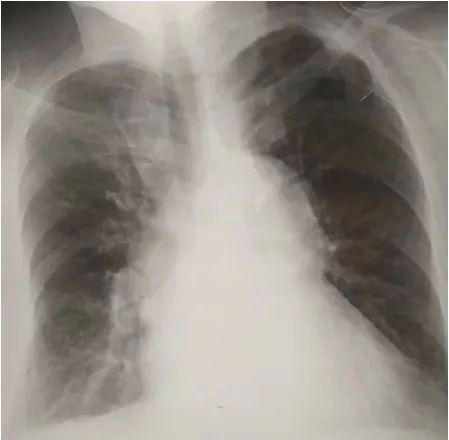

▶▷ 胸片